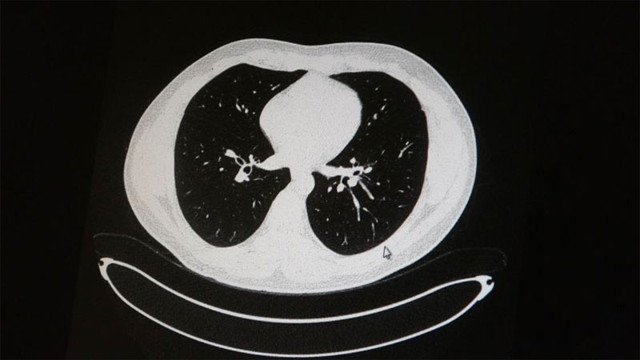

Uzm. Dr. Azar, aynı şekilde aşı olup korona virüs hastalığına yakalanan bir başka genç hastanın akciğer tomografisinde akciğerde herhangi bir sorunun olmadığını ve hastanın durumunun iyi olduğunu gözlemlediklerini kaydetti. Uzm. Dr. Azar, sürekli şahit oldukları "Keşke biz aşı olsaydık" sözünü bir daha duymamak için herkesi aşı olmaya davet etti.